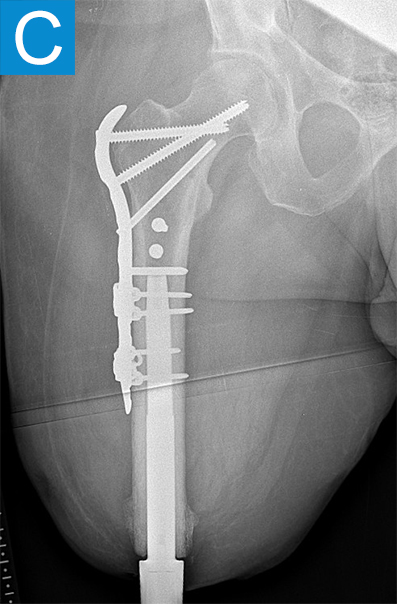

He started progressively loading the implant at 2 weeks and received his full prosthetic leg with simple hinged knee at 6 weeks. At 3 months he no longer used assist devices and at 3.5 months his prosthesis was changed to a microprocessor-controlled knee. Shortly after receiving the new knee, he stumbled stepping over a ledge and fell, sustaining a subtrochanteric proximal femur fracture (Figure 2b). The fracture extended to the tip of the implant, which remained stable in the bone. He underwent open reduction and internal fixation of the femur fracture with a proximal locking plate (Figure 2c). He did not wear the prosthetic leg for 10 weeks, when he began gradually loading the femur. He resumed full weightbearing without assistive devices about 6 weeks later.

Figure 2. Postoperative X-rays shows (A) a femoral osseointegration implant; (B) a subtrochanteric proximal fracture; (C) the femur fracture repaired by open reduction and internal fixation with a proximal locking plate.